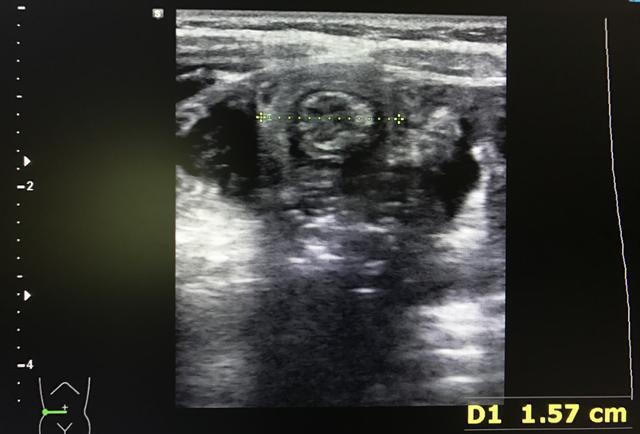

腹部肿物:发生回结肠套叠(发生率85%)时,在右上腹或脐上多可触及肿物,呈腊肠样的光滑实性肿物,有弹性且略可活动。